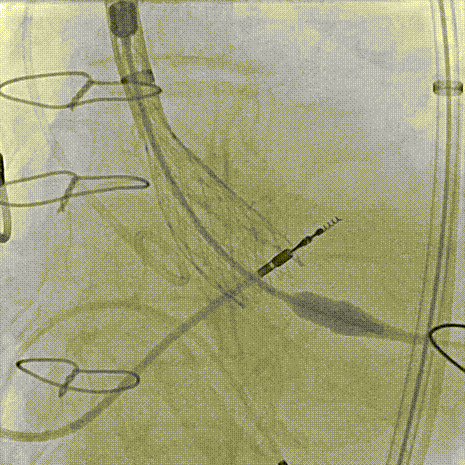

主动脉根部造影

80%工作位评估